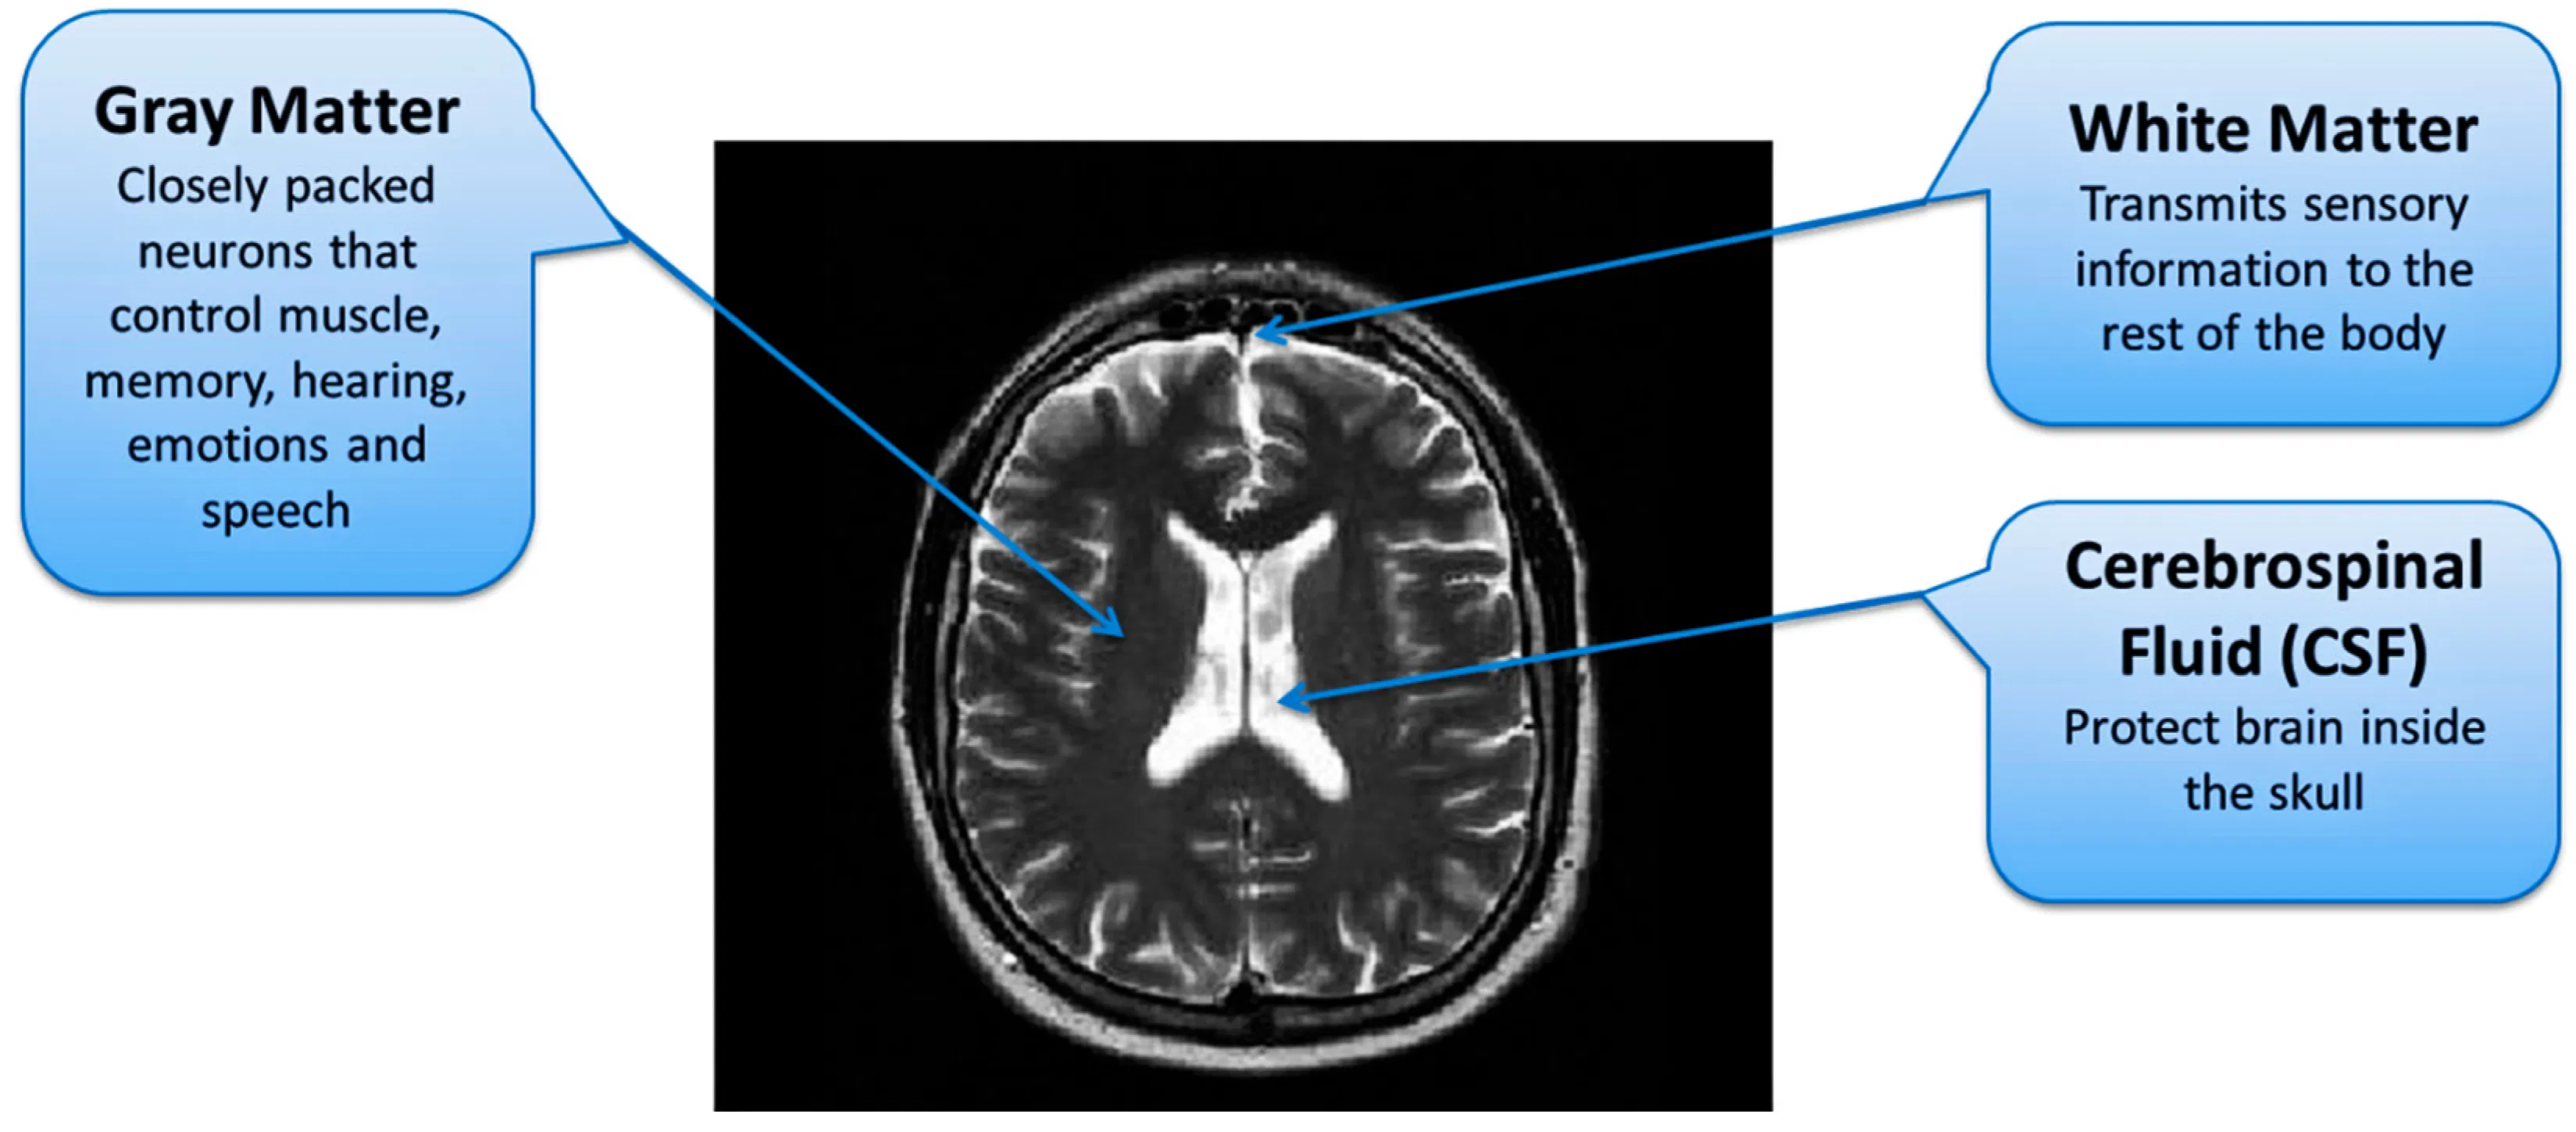

Nah, grey matter ini apa sih? Sederhananya, ini adalah bagian otak tempat pemrosesan informasi terjadi. Sekitar 40 persen otak kita terdiri dari grey matter, dan di sinilah sebagian besar struktur neuronal berada. Artinya, fungsi-fungsi otak yang paling penting berlangsung di sini.

Menurut Cleveland Clinic, grey matter adalah tempat di mana pemrosesan sensasi, persepsi, gerakan sukarela, pembelajaran, kemampuan berbicara, dan kognisi berlangsung. Bayangin aja—semua yang bikin kita bisa berpikir jernih, belajar hal baru, dan berkomunikasi dengan baik, semuanya bergantung pada grey matter yang sehat.

White Matter: Jalur Komunikasi Antar Bagian Otak

Studi yang sama juga menemukan bahwa terlalu banyak screen time mengurangi jumlah white matter, yaitu bagian otak tempat banyak komunikasi antar wilayah otak terjadi. White matter berwarna putih karena terbuat dari zat lemak bernama myelin yang membantu mempercepat komunikasi di seluruh otak.

Jadi bayangkan begini: grey matter itu seperti kantor-kantor yang memproses informasi, sementara white matter adalah jalan raya yang menghubungkan kantor-kantor itu. Kalau keduanya menyusut, ya otomatis kinerja otak jadi terganggu.